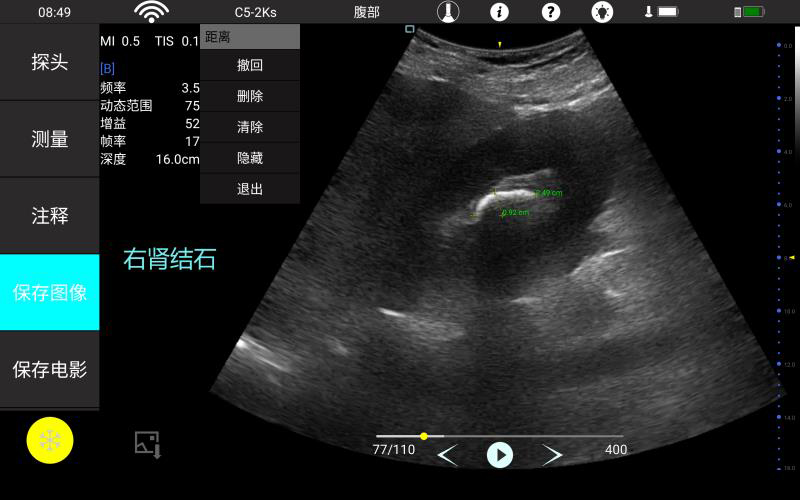

• 大凸

腹部

肾脏

妇科产科

心脏

肺等